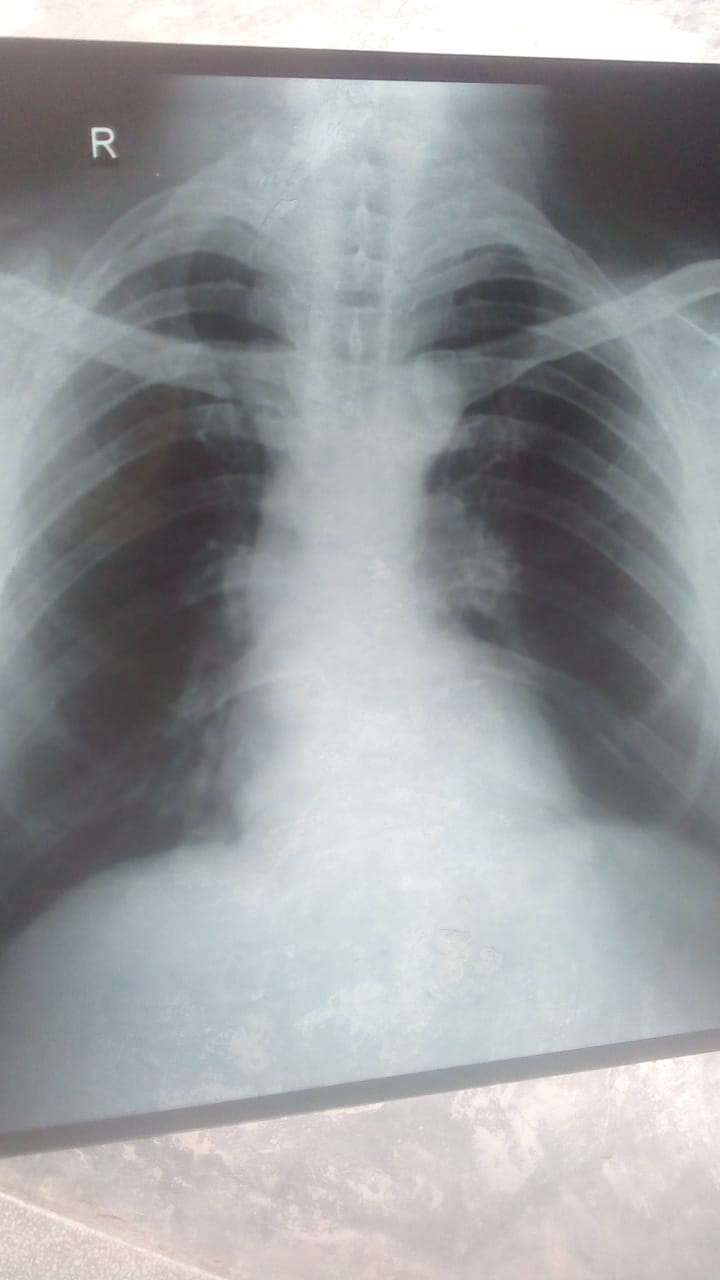

Doctor sahab, mera gala khraab hai kuch dinon se and balgham b aati hai iss k liye mene azomax shuru ki hai, mjhe tasalli nae hui issliye mene xray b krali chest ki, mjhe btayen me kia medicines loon or kia yeh xray chest ki normal hai ya mjhe doctor ko in person check krana chahye?

Visit medical or chest specialist early

get ur self examined by chest physcian